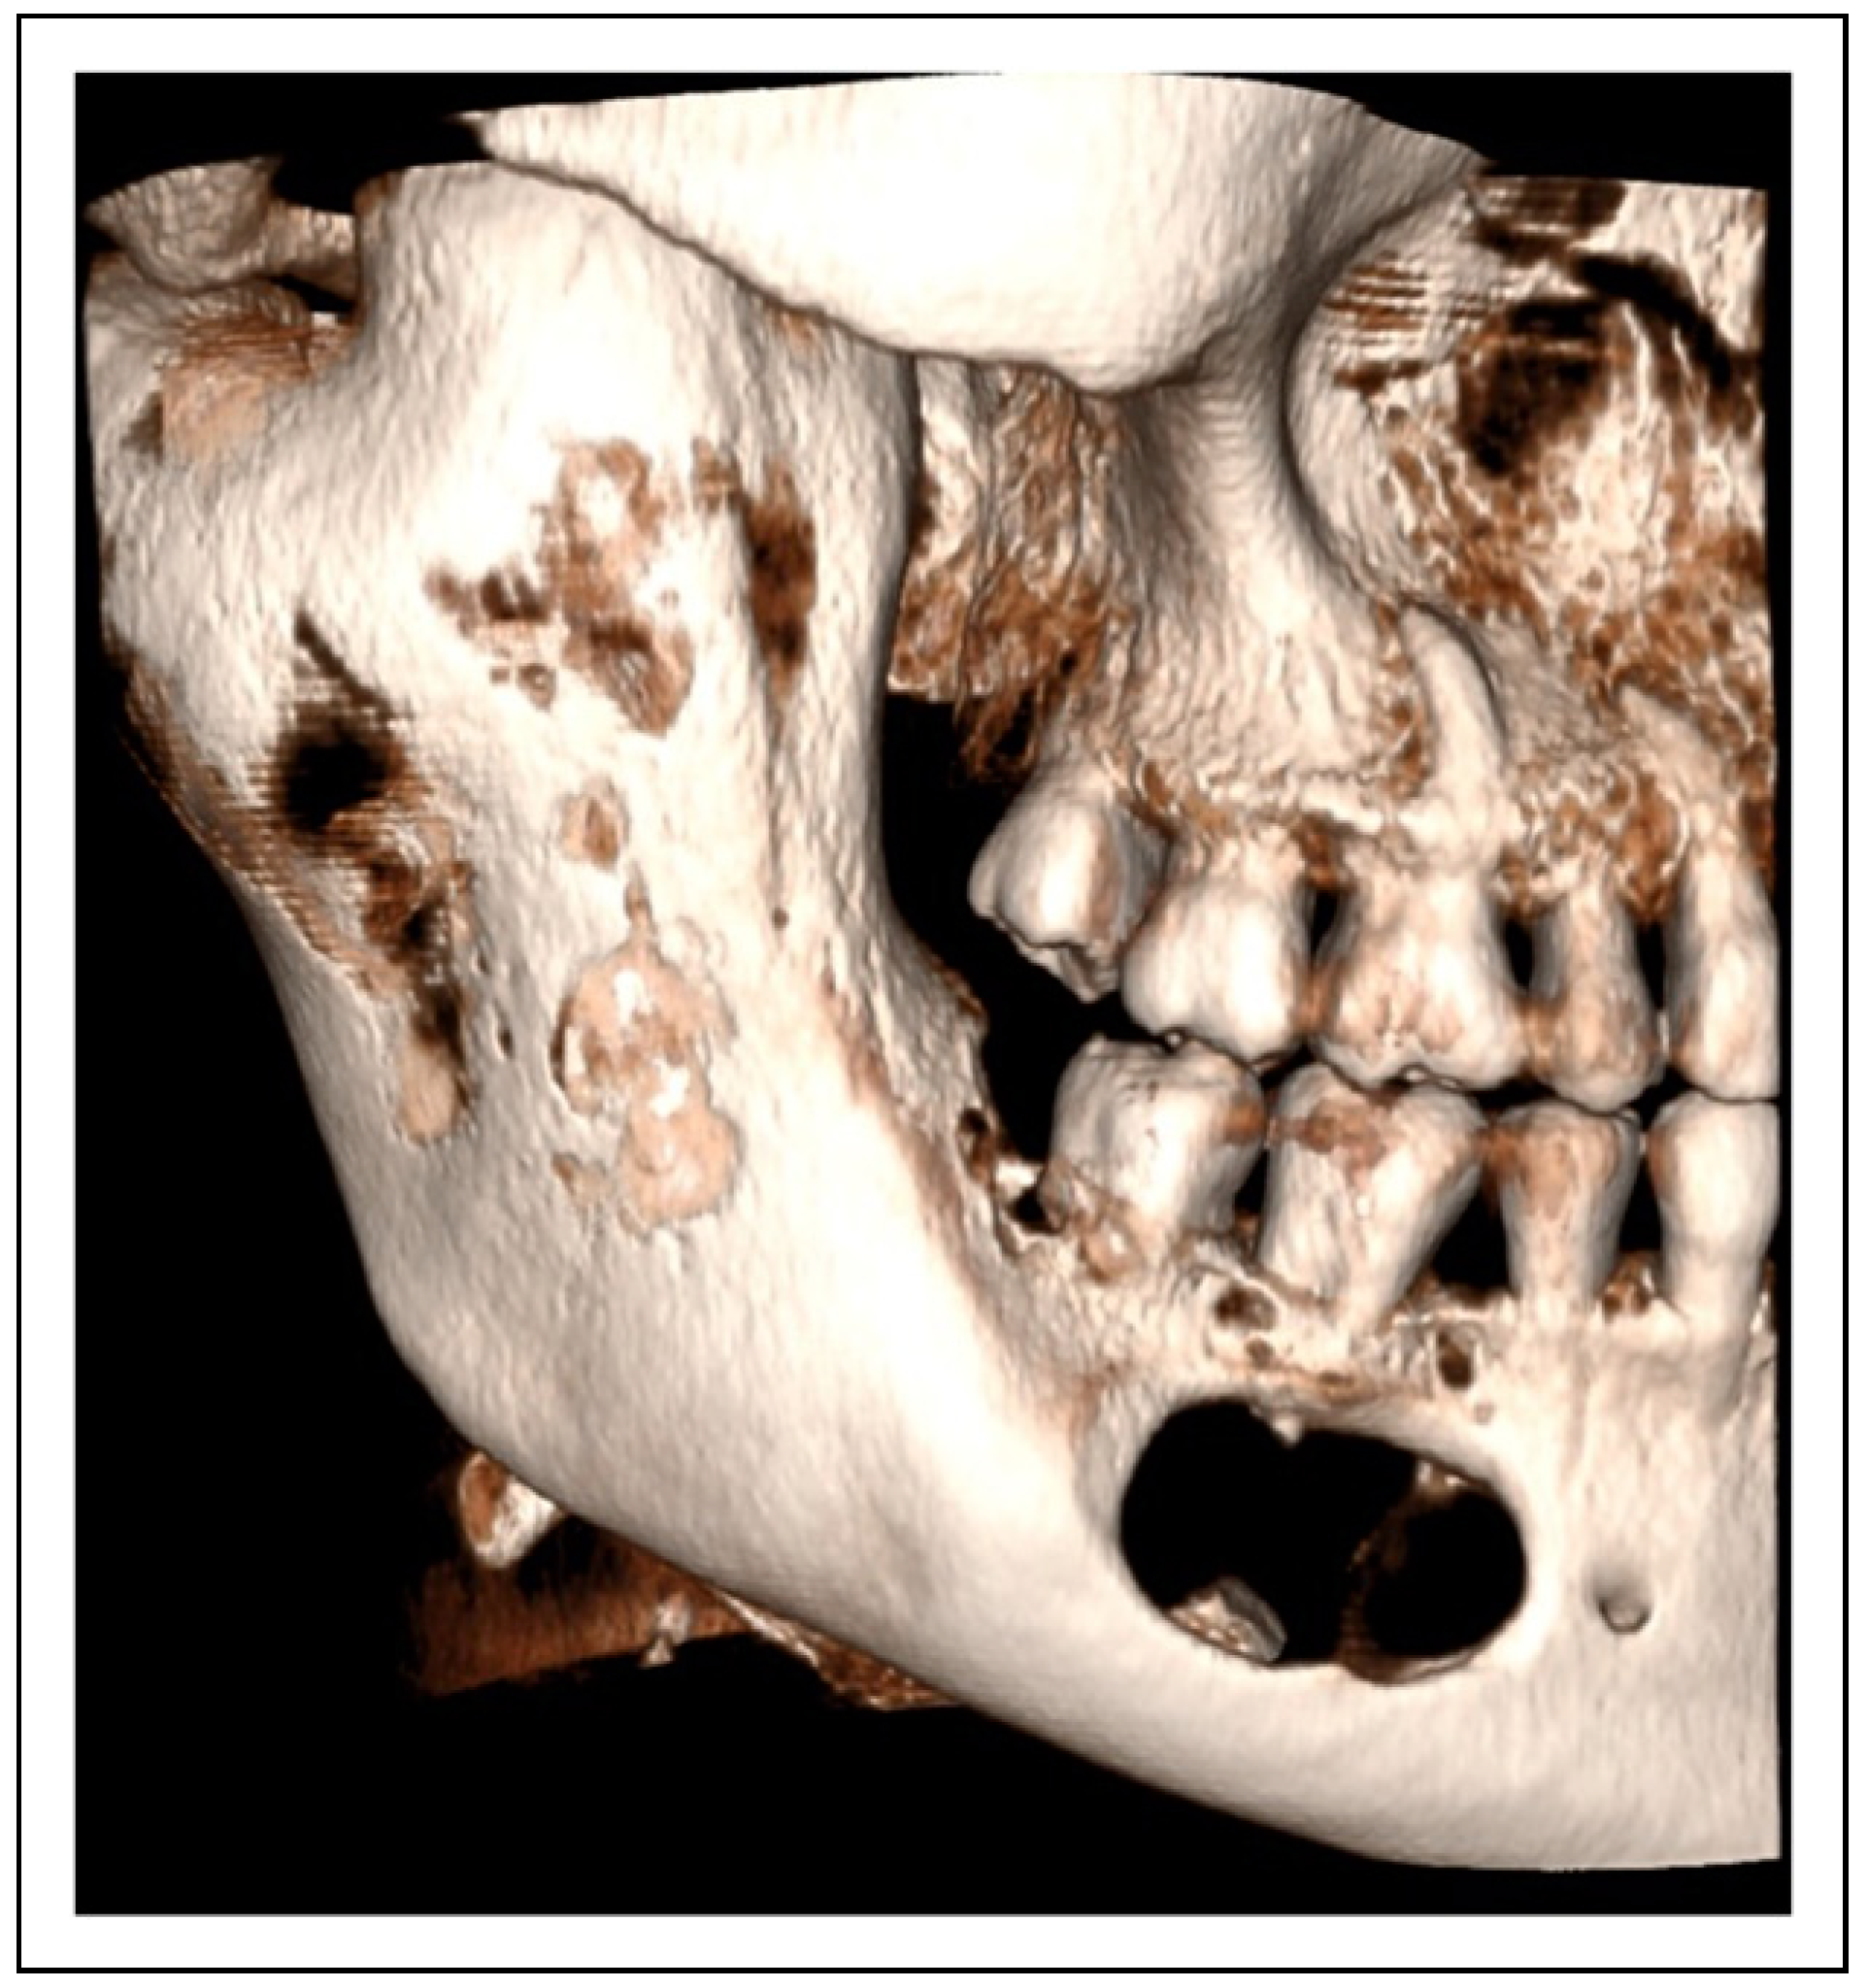

Two-Stage Regime, Patient 1